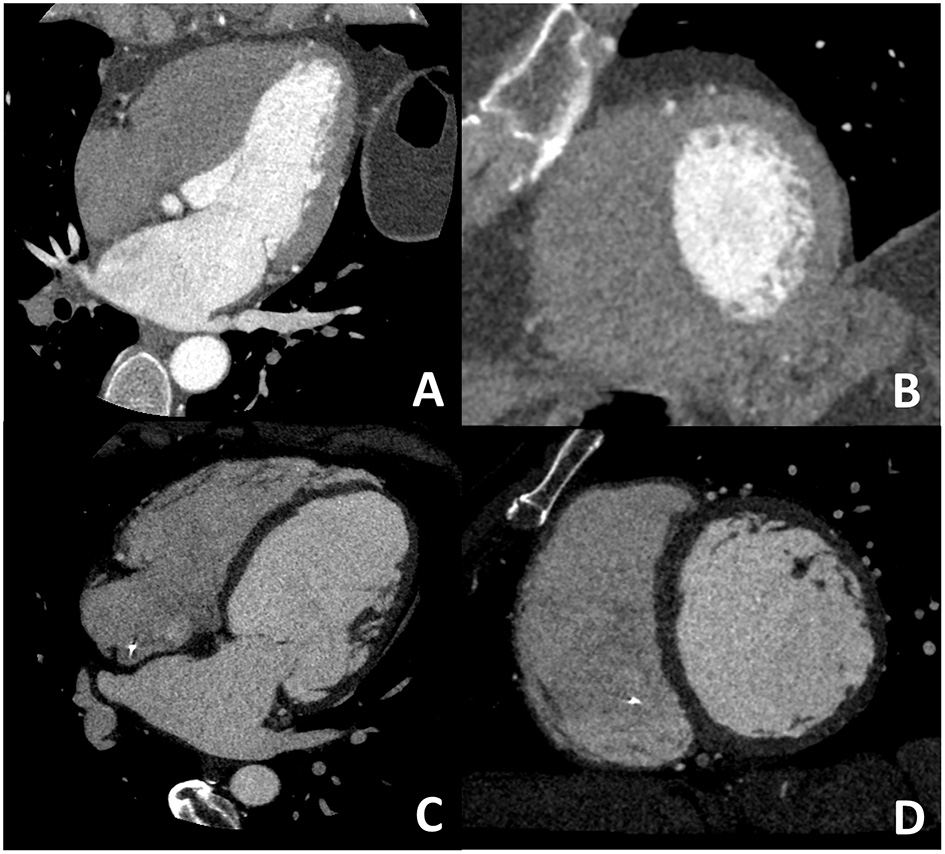

Figure 1

Coronary artery anatomy evaluation. A case example of 65 years old female patients with newly diagnosed severe reduction of left ventricular ejection fraction (<30%), symptomatic for dyspnea. Cardiac CT was performed with optimal image quality (A). A severe multivessel coronary artery disease was found with a subocclusive lesion on mid-left anterior descendent artery (B), significative lesion on left-circumflex artery (C), no significative lesion on the marginal branch and subocclusive disease on right coronary artery (D,E).